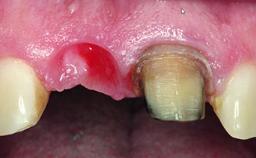

Replacement of a Perforated Upper Left Central Incisor: Early Placement of an RC Bone Level Implant

A 28-year-old patient presented at her general dentist’s office and complained about the appearance of her tooth 21. The patient had a history of trauma to this tooth. Endodontic treatment had been performed in the past and a crown placed on the tooth. A procedure to replace the old crown was performed by her dentist; however, a perforation on the middle third of the root occurred, and extraction of tooth 21 was suggested. Upon clinical and radiographic examination of the patient, who had been referred to us, replacement of tooth 21 by a dental implant appeared to be indicated.

Soft Tissue Grafting Staged